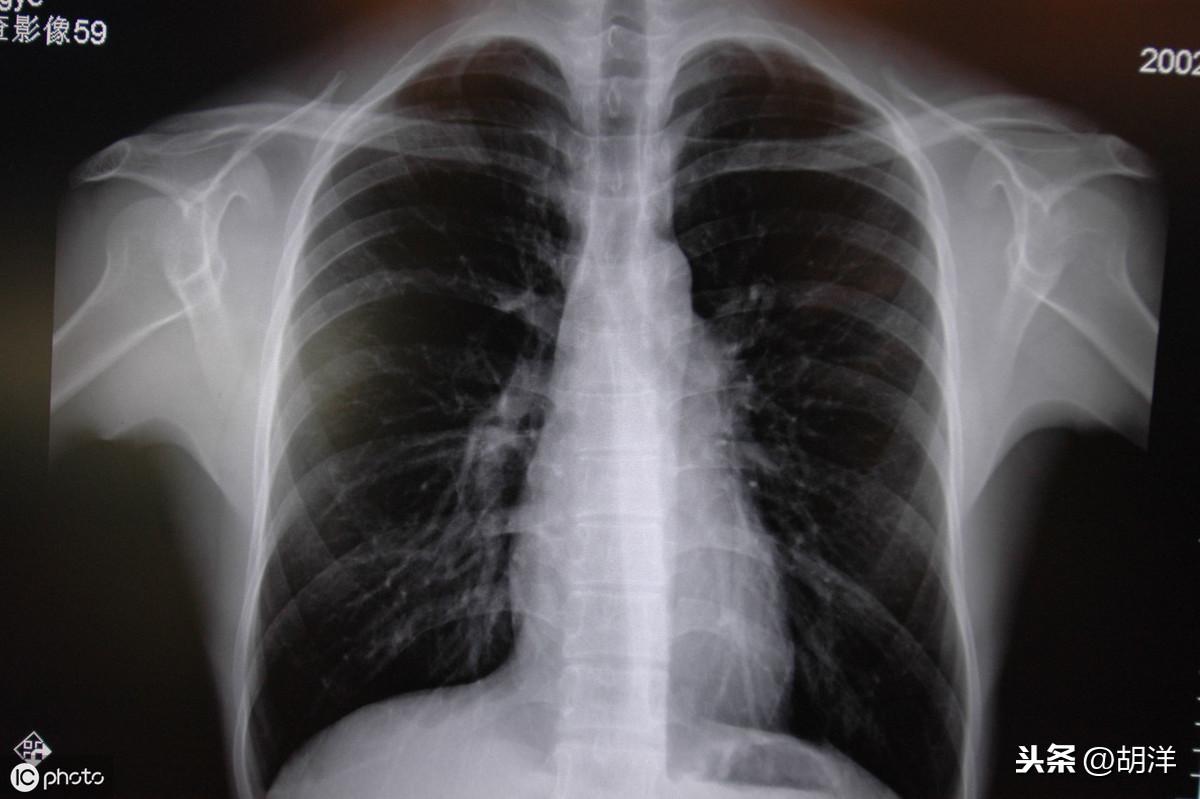

常德肺炎最新动态,背景、事件进展与影响概述

摘要:最新常德肺炎是指发生在常德地区的肺炎疫情。其背景可能与地区气候变化、人群免疫力下降等因素有关。事件方面,包括疫情的发现、传播情况、防控措施等。该疫情的影响涉及到当地居民的健康、社会经济等方面,可能带来一定程度的...